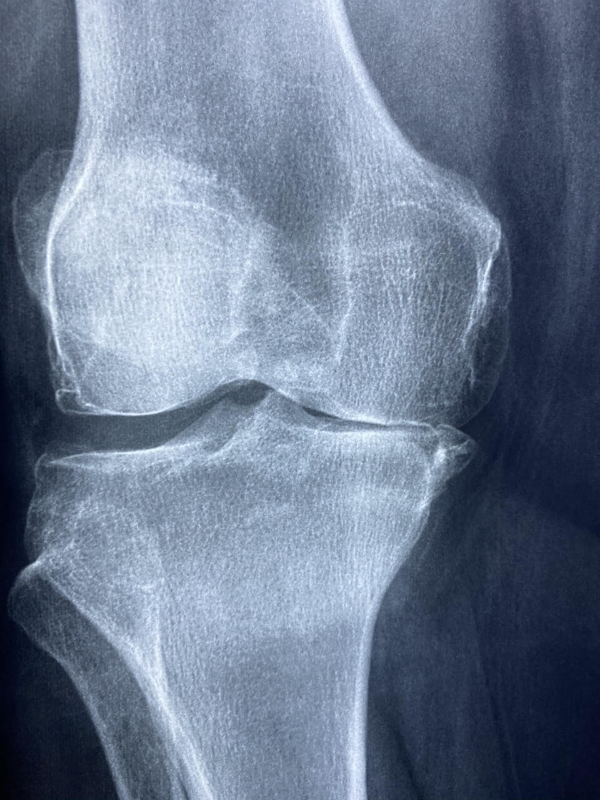

4. 병원에서는 어떻게 진단할까?

연골 손상이 의심되면 병원에서 아래와 같은 검사를 통해 상태를 정확히 확인합니다.

- X-ray 검사 - 뼈 간격 감소나 관절염 여부 확인

- MRI 검사 - 연골 상태 확인에 가장 정확한 검사

- 관절초음파 - 연골 주변의 염증, 부종 확인

- 기능 검사 - 보행, 관절 가동범위, 근력 평가

특히 MRI는 연골 상태를 눈으로 확인할 수 있어 진단에 큰 도움이 됩니다.